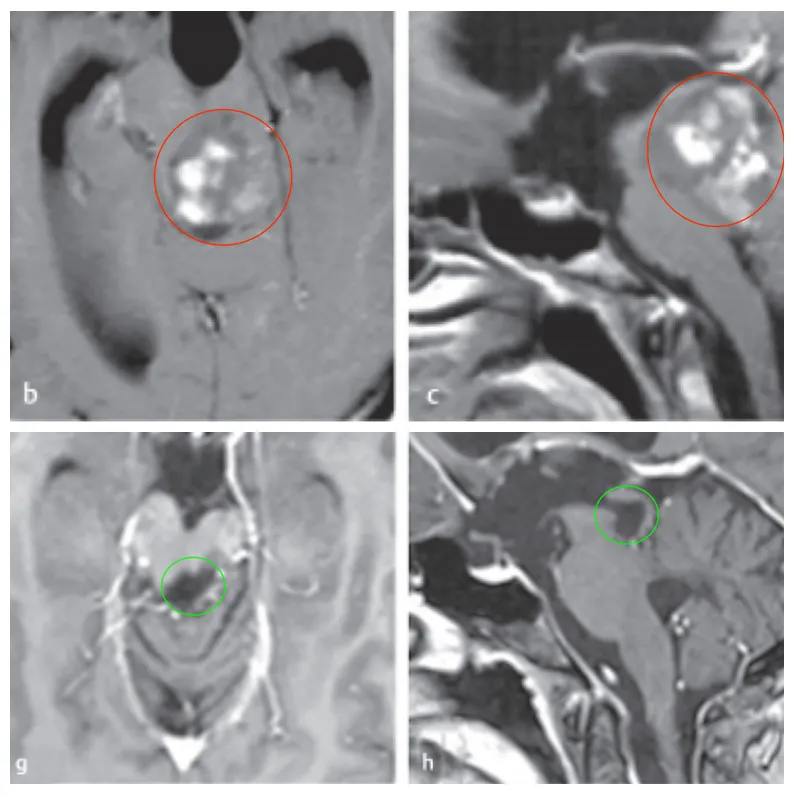

由于肿瘤与周围的脑干实质有很好的边界,巴教授术中肿瘤全切,术后MRI复查明确未见肿瘤残余。术后11年随访时:术后MRI显示患者没有肿瘤残留或复发。患者的临床状况良好,眼球运动正常。随访至今,她为自己赢得了19年无复发,状况非常好。

图:术前术后脑磁共振对比,脑干胶质瘤全切,无神经脑组织损伤。

30岁女士,有复视和轻微右侧偏瘫,a、b图患者术前MRI显示中脑肿瘤,患者最初接受立体定向囊肿抽吸和间质放疗,并被诊断为毛细胞型星形细胞瘤,但肿瘤仍在生长。

巴教授为其手术,无手术并发症,f图显示伤口愈合正常,患者预后良好,无神经功能缺损。组织病理学检查为1级毛细胞型星形细胞瘤。g、h图术后MRI影像显示,肿瘤全切。随访MRI记录手术后9年无肿瘤复发。